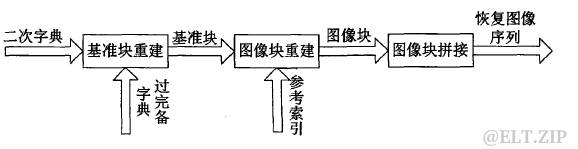

解压缩流程如下:

图五.基于稀疏表示的序列图像解压缩流程